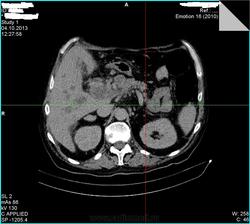

- https://radiomed.ru/sites/default/files/styles/case_slider_image/public/user/15361/00bd452f.jpg?itok=7Yqpn566

- https://radiomed.ru/sites/default/files/styles/case_slider_image/public/user/15361/00bfee95.jpg?itok=PUcrVzyc

- https://radiomed.ru/sites/default/files/styles/case_slider_image/public/user/15361/00c0937f.jpg?itok=7U4D1tv_

- https://radiomed.ru/sites/default/files/styles/case_slider_image/public/user/15361/00ca7eed.jpg?itok=rr_xi6tP

- https://radiomed.ru/sites/default/files/styles/case_slider_image/public/user/15361/00cb6df1.jpg?itok=1nPv330F

- https://radiomed.ru/sites/default/files/styles/case_slider_image/public/user/15361/00cb352d.jpg?itok=EVSnuZCO

- https://radiomed.ru/sites/default/files/styles/case_slider_image/public/user/15361/00cce936.jpg?itok=PqpE7v3O

- https://radiomed.ru/sites/default/files/styles/case_slider_image/public/user/15361/00cd0fba.jpg?itok=XHp74aU2

- https://radiomed.ru/sites/default/files/styles/case_slider_image/public/user/15361/00cd29f9.jpg?itok=H17OxJCX

Контраст тоже не завезли? Блок БДС возможен.

Тоже вижу расширенные желчные протоки. Освойте экспорт изображений в формате дайком, тогда сможете размещать из на сайте, советы будут более предметными.

+1. Дайте дайкомы посмотреть. Возможна обструкция интрапанкреатической части холедоха или еще ниже. А для итерпретации очагов в печени желательно контрастное усиление сделать.

При патологии печени очень желательно указывать наличие/отсутствие болевого синдрома, желтухи. Большинство КТ-исследований гепато-панкреато-дуоденальной зоны (а эта зона является одной из самых трудно трактуемых в брюшной полости) без контраста является мало информативным способом облучения пациента . Фокусные изменения и расширение внутрипеченочных желчных протоков было видно и на УЗИ. Понятно, что не всегда есть контраст, но ... в-общем, попробуем выжать максимум из имеющегося, если у Вас получится закинуть архив дайкома на файлообменник.

. Фокусные изменения и расширение внутрипеченочных желчных протоков было видно и на УЗИ. Понятно, что не всегда есть контраст, но ... в-общем, попробуем выжать максимум из имеющегося, если у Вас получится закинуть архив дайкома на файлообменник.